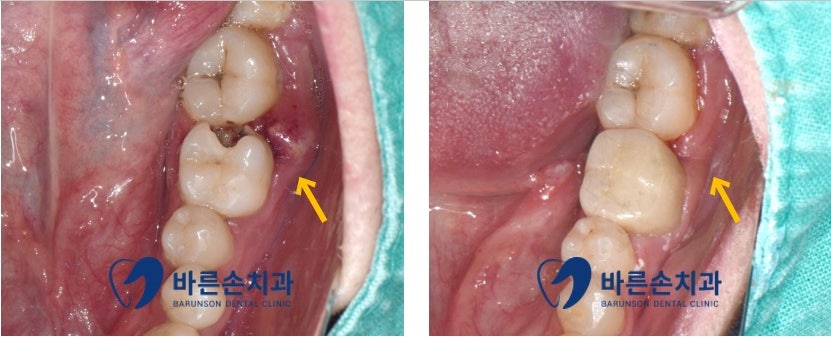

처음 내원 당시 육안 사진입니다

충치로 인한 치아 파절과 염증으로 인한 잇몸 발적 및 부종이 있으며

이로 인해 환자분께서 극심한 통증을 호소하고 있는 상태였습니다

신경치료 완료 후 약해진 치아를 보강하기 위해

내 치아처럼 자연스럽고 튼튼한 지르코니아 크라운으로 마무리하였습니다

더불어, 염증이 있던 주변 잇몸도 잇몸치료를 통해 건강한 잇몸으로 회복되었습니다^^